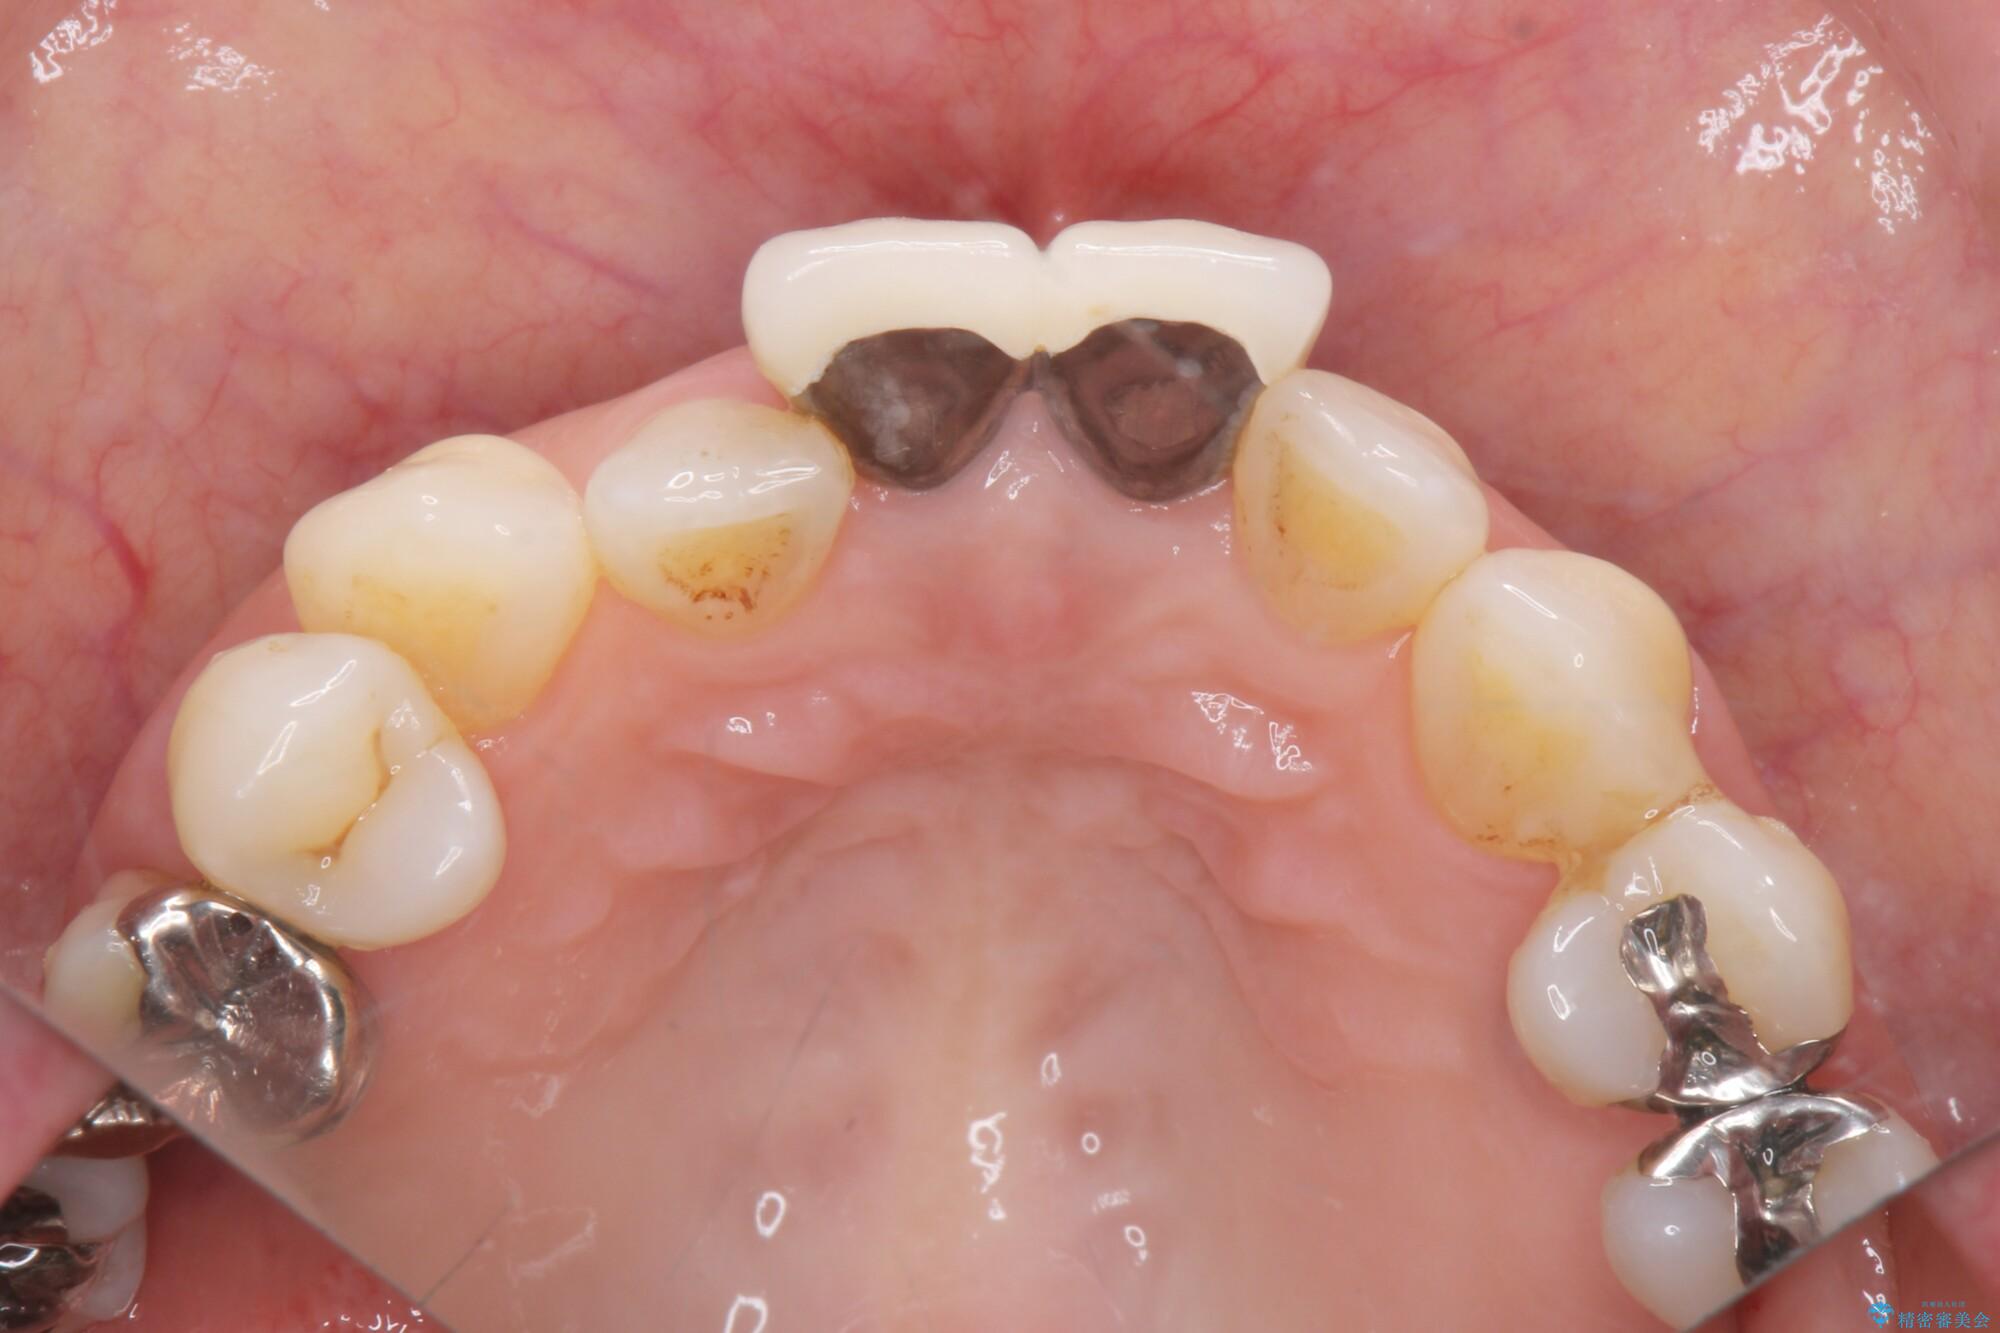

前歯の差し歯(クラウン)が黒ずんでいるとご相談にいらっしゃった患者様です。

根管治療は行わず、クラウンのやり替えのみ行います。